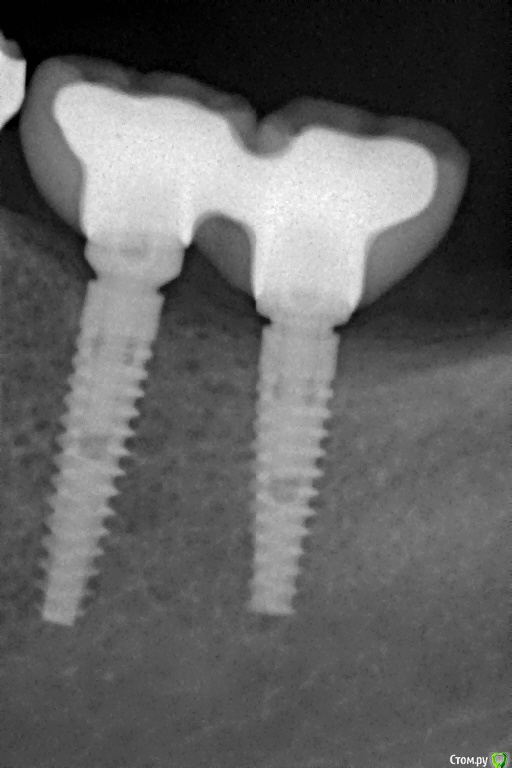

Pavel-Pskov Опубликовано 24 мая, 2016 Поделиться Опубликовано 24 мая, 2016 В момент снятия слепков май 2014 г.Неделя назад Ссылка на комментарий